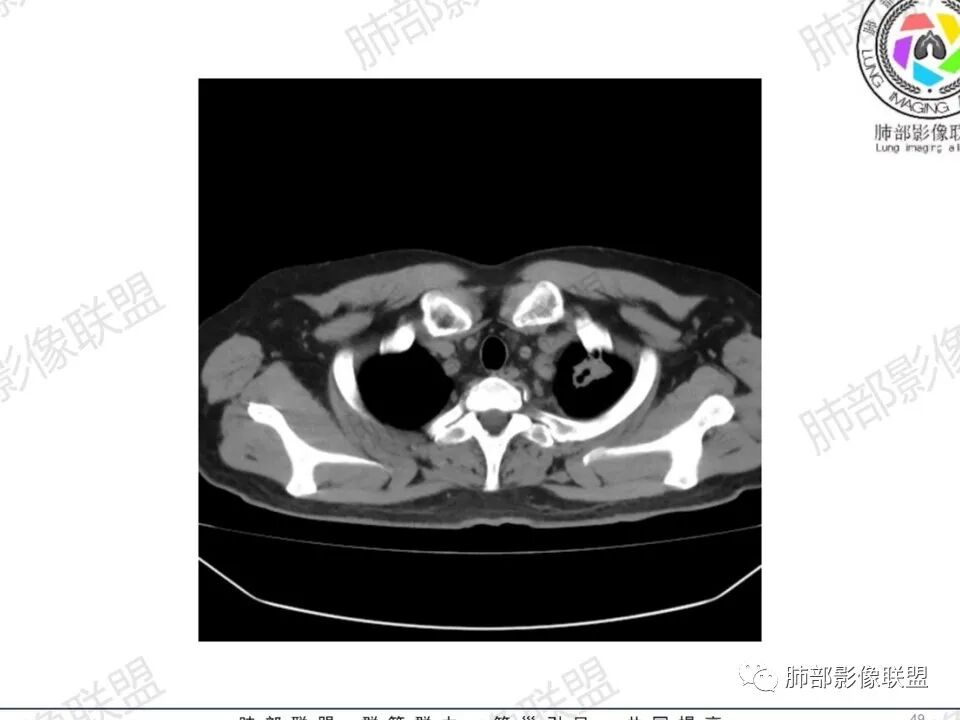

双肺多发结节,胸膜下为主,部分可见空洞。左肺上叶尖后段结节较大,分叶毛刺,周围可见长条索及小斑片影,内空洞比较光滑,内侧壁可见支气管通过。右肺下叶后基底段不张实变,后侧积液,右侧水平裂积液,右侧膈胸膜纵膈胸膜增厚积液,右侧侧胸膜肥厚,考虑1:一元金葡。2二元:金葡,左肺上叶结核。

男,45岁,左手指红肿疼痛两天,右侧胸壁疼痛伴发热12小时入院。患者急性起病,胸部CT示双肺多发结节,部分伴空洞,空洞壁较光滑,右侧胸腔积液,考虑感染性病变,金葡菌加SPE可能

中年男性,左手中指及胸壁疼痛伴发热来诊,影像见双肺多发结节,胸膜下分布为主,部分结节可见空洞,边缘模糊。左肺上叶尖后段结节较大。右肺下叶后基底段不张实变,右侧叶间裂及右侧胸腔积液,右侧侧胸膜肥厚。考虑金葡菌感染,血播SPE。

两肺多发结节空洞,随机分布,右肺下叶部分病灶实变并胸膜腔少量积液,有皮肤破溃,手指疼痛,发热,考虑感染性变,金葡可能性大。

胸膜下为主多发结节,边缘光滑

胸水,部分包裹

支持血道来源感染性病变,金葡菌肺炎首选